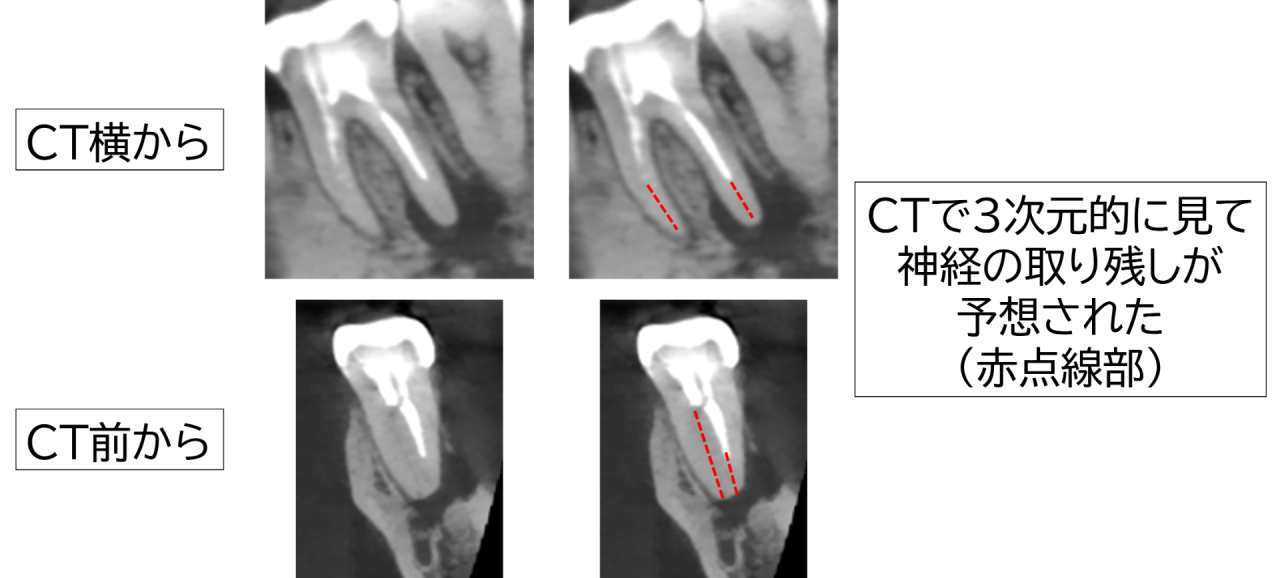

レントゲン(CT)撮影で詳細に確認しました。根の先に大きな病気とみられる透過像(黒い影)が認められ、骨が広い範囲で溶けてしまっている状態でした。診断は「慢性根尖性歯周炎」。

原因は神経の取り残しと考えられました。取り残された神経が死んで腐敗し、細菌が増殖して根の病気を作ったのです。

口腔内をラバーダムで乾燥・隔離し、マイクロスコープ(顕微鏡)拡大視野下で根管の入口と分岐部を観察。取り残しの神経の部位を確認しました。